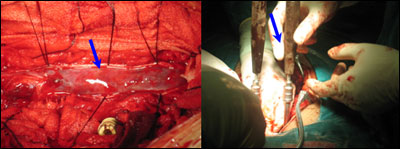

术后:感觉平面下降,腰痛缓解;随访发现臀部疼痛加重,伴便秘,双下肢肌力减弱,在他人扶持下行走。患者术后2月来院要求二次手术解除腰椎管内占位。术中见肿瘤位于硬膜下、部分来自圆锥髓内,紫红色,血运丰,向各椎间孔、隙浸润生长,全切肿瘤后,考虑脊柱的稳定性受影响,予以内固定治疗。术后病理回报为室管膜瘤,将第一次病理片子送到外院复审,认为其形态符合室管膜瘤,两处病变是同一性质的肿瘤。